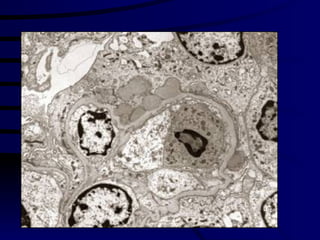

3.Electron Microscopic Investigation study  disorders at an organelle level and subcellular details.  transmission and scanning EM

3.Electron Microscopic Investigationstudy disorders at an organelle level and subcellular details. transmission and scanning EM